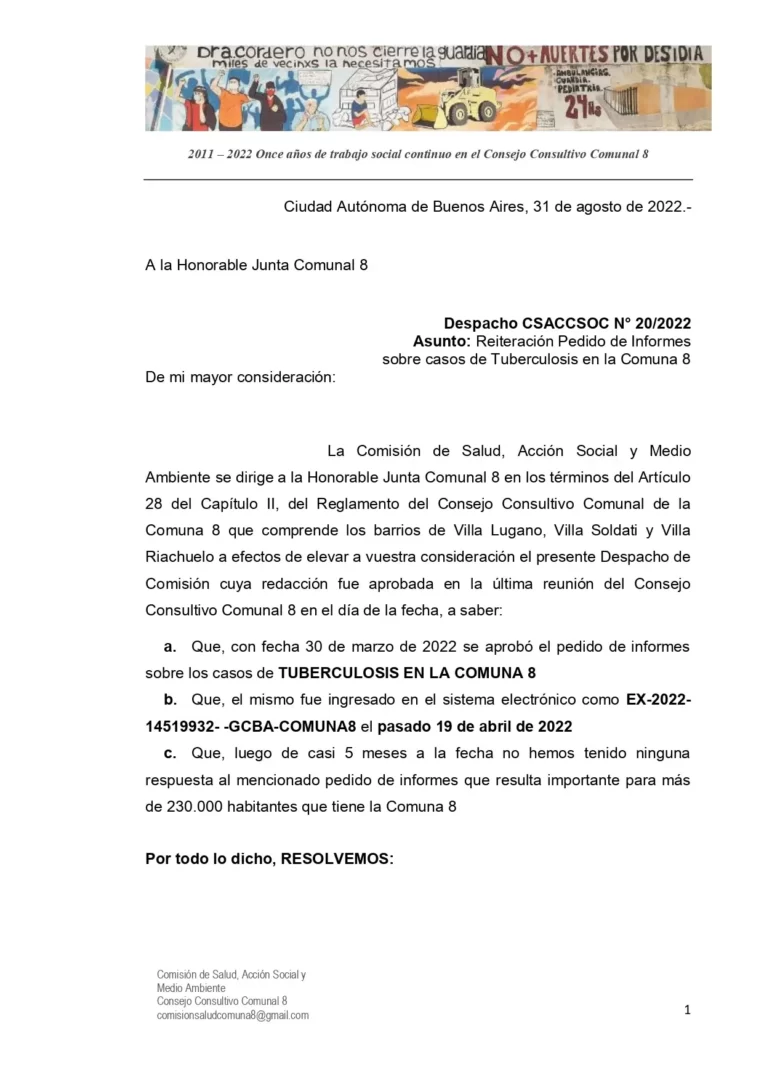

Es una enfermedad contagiosa que desde hace muchos años se encuentra en nuestra Comuna 8 y en el sur de la Ciudad

Hace tiempo que no recibimos el informe “segmentado” de cada Comuna por lo tanto, nos vemos en la necesidad de solicitar una vez más, un pedido de informes

En este caso, lo que hacemos es reiterar uno que ya hicimos este año y no respondieron nada